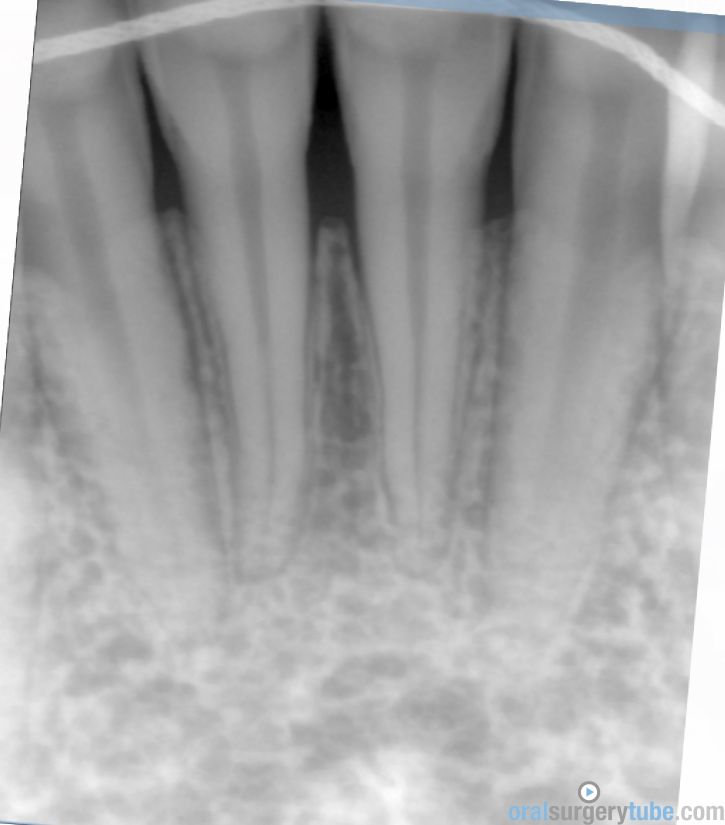

Paciente joven acude para consultar acerca de recesión gingival pieza 31 (clase II Miller). Paciente deja constancia de la importancia de la estética para ella. Hace unos 6 meses, se le realizó cirugía mucogingival con injerto conectivo palatino (la cuál fue fallida, ya que la recesión permanece)... Refiere además cierta molestia al traccionar del labio.

Al movilizar el labio, me transmite la sensación de haber quedado una inserción de fondo de vestíbulo alta... Pienso que podría ser debido a no haber realizado una desinserción muscular al reponer el colgajo coronalmente? (Foto 2). Considero que aún mantiene cierta cantidad de banda queratinizada, pero realmente mínima.

Dado a que se trataría de realizar una "reentrada" o retratamiento (no tengo experiencia hasta la fecha de haber tenido que retratar ningún caso de mucoginigval), agradecería toda opinión acerca de la técnica que más idónea consideréis... Teniendo en cuenta esas posibles adherencias musculares, el biotipo, la demanda estética de la paciente, no sé si lo ideal es tratar con injerto conectivo tipo "técnica bilaminar" y desinsertar la musculatura, o un Injerto de Encía Libre (FGG) y reponer apicalmente la musculatura...

La duda que me surge con el injerto conectivo es si el colgajo me permitiría ser reposicionado coronalmente, teniendo en cuenta esa sensación de "tirantez" actual que describe el paciente. Y la duda de realizarlo con FGG es si conseguiría cubrir la recesión por completo, y si es adecuado para ese solo diente...